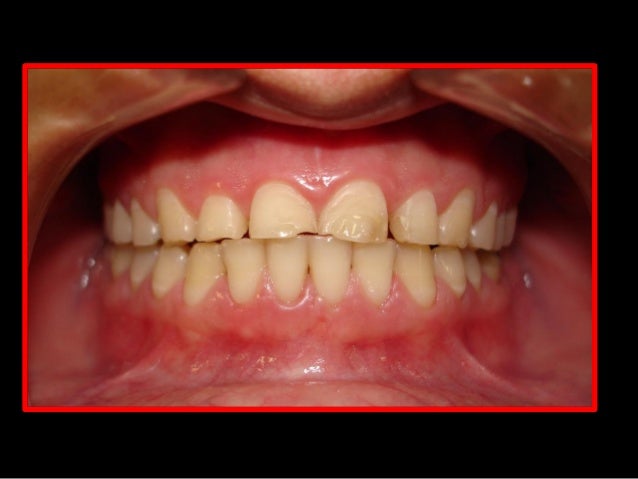

21. 21. Classe I -Normoclusão

22. 22. Classe II- Maxila avança a Mandíbula

23. 23. Classe III-Mandíbula a frente da Maxila

24. 24. Mordida Cruzada- Mandíbula cobre parte da Maxila

25. 25. Mordida Profunda- Maxila cobre muito a Mandíbula

26. 26. Mordida Aberta- Os dentes não se tocam

27. 27. Apinhamento- Não há espaço para os dentes